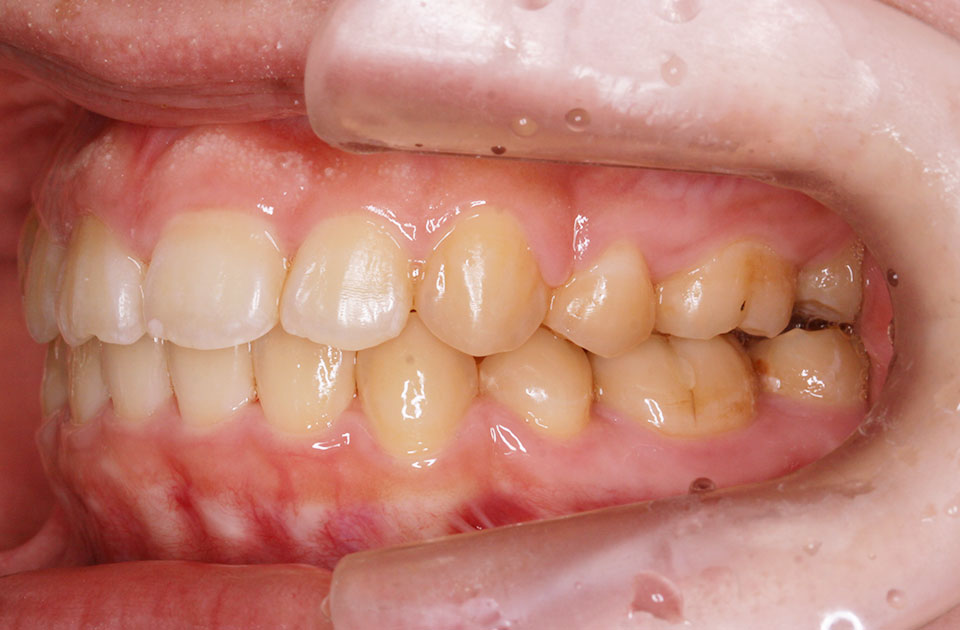

矯正前 右側

矯正後 右側